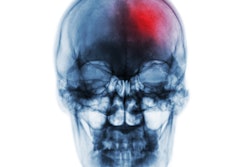

About five weeks after her tooth was pulled, the woman was taken to the emergency department after she was having trouble speaking and the right side of her face was drooping.

She underwent a computed tomographic angiography that showed a left segment middle cerebral artery occlusion “with reconstitution of the distal middle cerebral branches through arterial collaterals.” The blood clot was successfully removed, and her language and neurological deficits improved. Additional imaging revealed deep hemorrhages in the brain, they wrote.